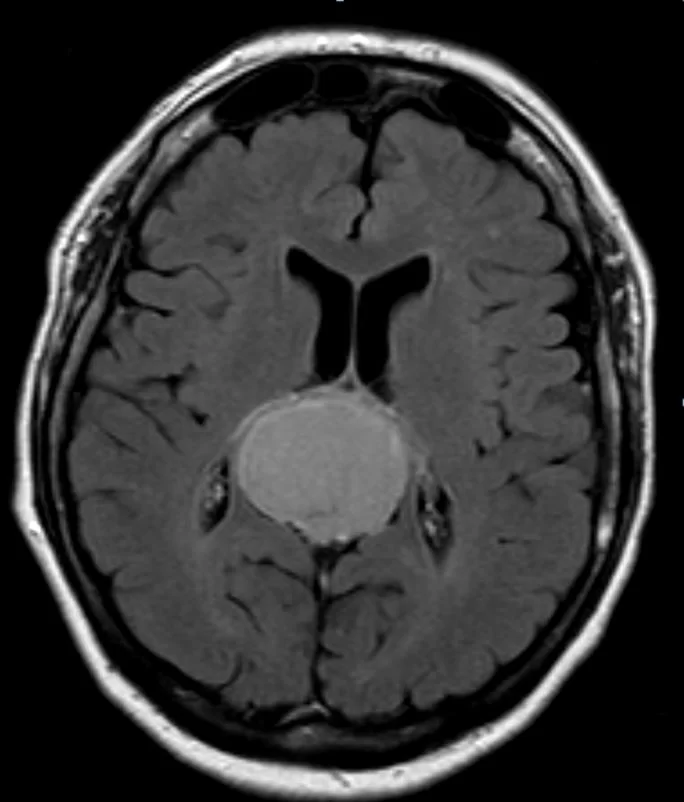

Ο απεικονιστικός έλεγχος με μαγνητική τομογραφία ανέδειξε ευμεγέθη όγκο στην περιοχή της επίφυσης (κωνάριο) με πίεση επί του μεσολοβίου, του τετραδύμου πετάλου και λοιπών εν’ τω βάθει δομών.